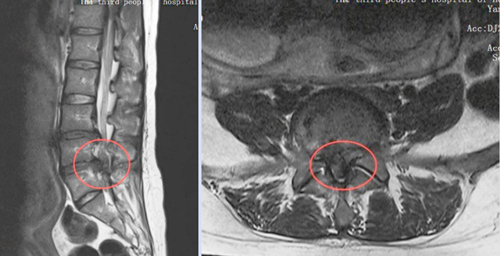

当地医院诊断后,结果令全家心弦紧绷——这不是普通的孕期不适,而是由严重腰椎间盘突出引发的“马尾神经综合征”。

这是一种急症,若不及时处理,可能导致永久性的下肢瘫痪、大小便功能障碍。更棘手的是,李女士还怀着宝宝。

在多学科团队的精密配合下,李女士接受了超声引导下的腰椎微创手术。